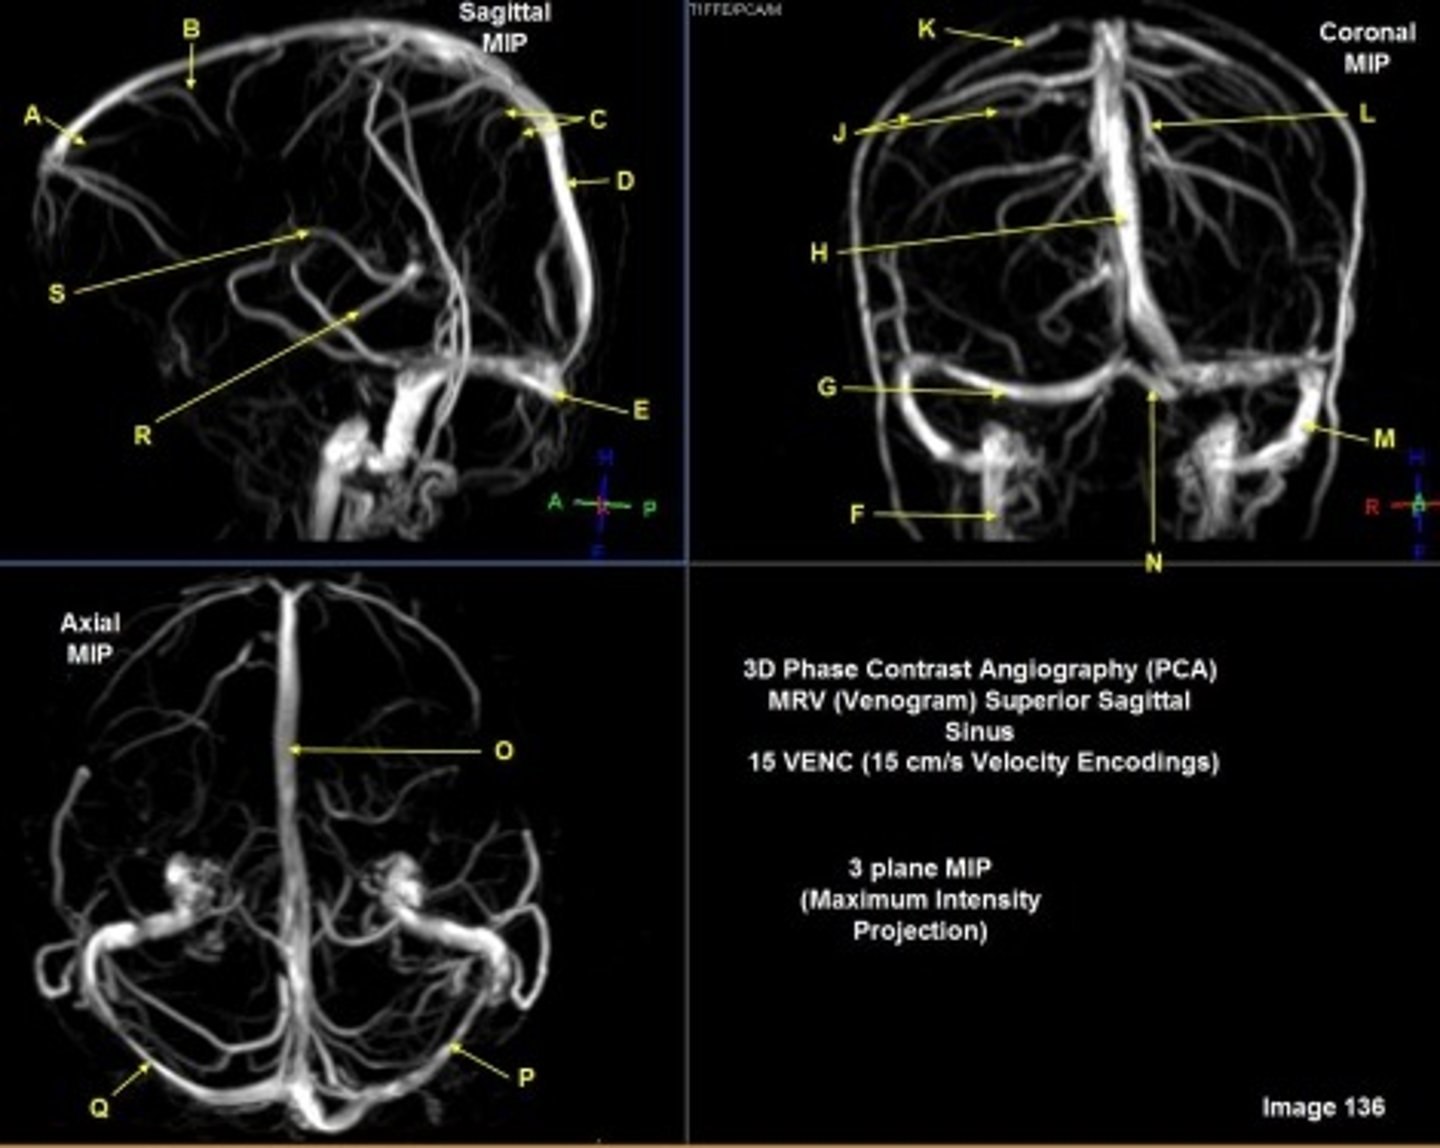

B

posterior frontal vein

C

parietal veins

D

superior sagittal sinus

E

Torcular herophili

F

internal jugular vein

G

R transverse sinus

H

J

R parietal veins

L

L parietal veins

K

Vein of trolard (superior anastomotic vein)

M

Left sigmoid sinus

N

O

P

Left transverse sinus

S

Internal cerebral vein